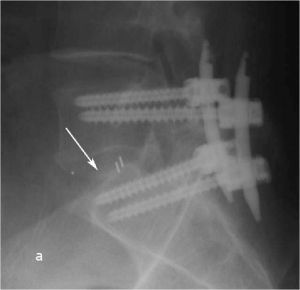

При рентгенографии (Рис.7) и МРТ (Рис.8) поясничного отдела позвоночника выявляется дегенеративный ретролистез L5 позвонка, секвестрированная парамедианная грыжа мп диска L5-S1 слева.

| Рис. 7а,b. Рентгенограмма поясничного отдела позвоночника в боковой (а) и прямой (b) проекциях до операции. Стрелкой показано смещение тела L5 позвонка кзади. | |

Пациенту выполнено оперативное лечение: удаление секвестрированной парамедианной грыжи мп диска L5-S1 слева из минидоступа, миниинвазивная транспедикулярная фиксация L5-S1 титановой конструкцией.

При контрольной рентгенограмме отмечено правильное положение транспедикулярной системы и кейджа на уровне L5-S1 позвонков. (Рис.9)